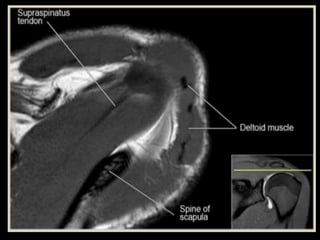

• 71.

• 85.

• 120.